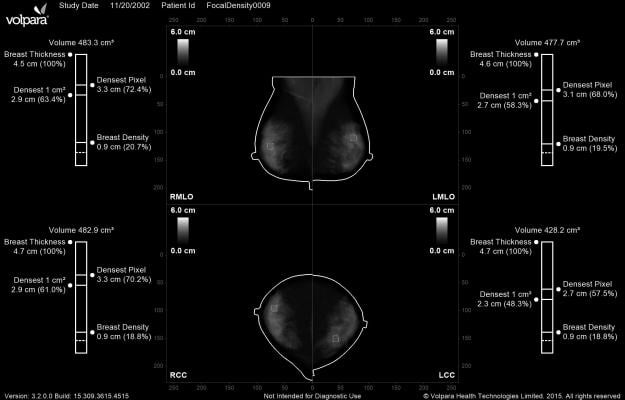

Volpara Density Maps present the 3-D quantitative volumetric information created by the VolparaDensity algorithm in a 2-D image that is available as an additional DICOM secondary capture image. Going beyond the measurement of the area of dense fibroglandular tissue, VolparaDensity measures the compressed thickness and volume of dense tissue, which enables the software to highlight specific parts of the breast tissue that are especially dense, including marking the densest 1-2 cm region of the image that might warrant closer inspection due to the masking risk.

Beyond masking risk, “For Presentation” images used for cancer detection are often displayed zoomed in, with heavy image processing, making it difficult to judge breast density, especially density changes over time. Volpara Density Maps are designed to show true breast density at true size, providing a standardized means of visually assessing which regions of dense tissue change over time.